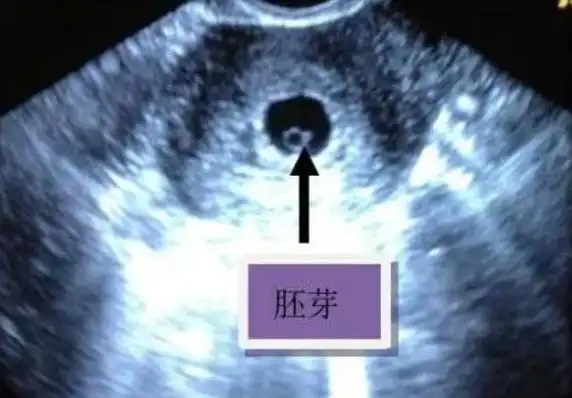

一般在停经42天左右,孕囊中可以出现胚芽,这个胚芽将会逐渐发育成为